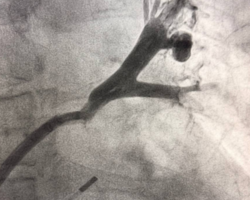

Вмешательство проводилось через бедренный венозный доступ под местной анестезией. Основная сложность операции заключалась в полной окклюзии обеих легочных вен и необходимости точной навигации инструментов в условиях ограниченной визуализации. После реканализации поражённых участков были имплантированы стенты, обеспечившие надёжное восстановление просвета сосудов и полноценный венозный отток из лёгких.

В результате кровоток по левой верхней и левой нижней легочным венам полностью восстановлен. Состояние пациента стабилизировалось, одышка регрессировала. В настоящее время пациент чувствует себя хорошо.